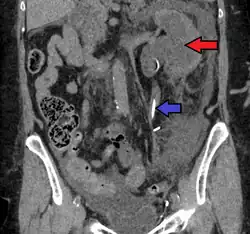

Stone causing hydronephrosis[16]